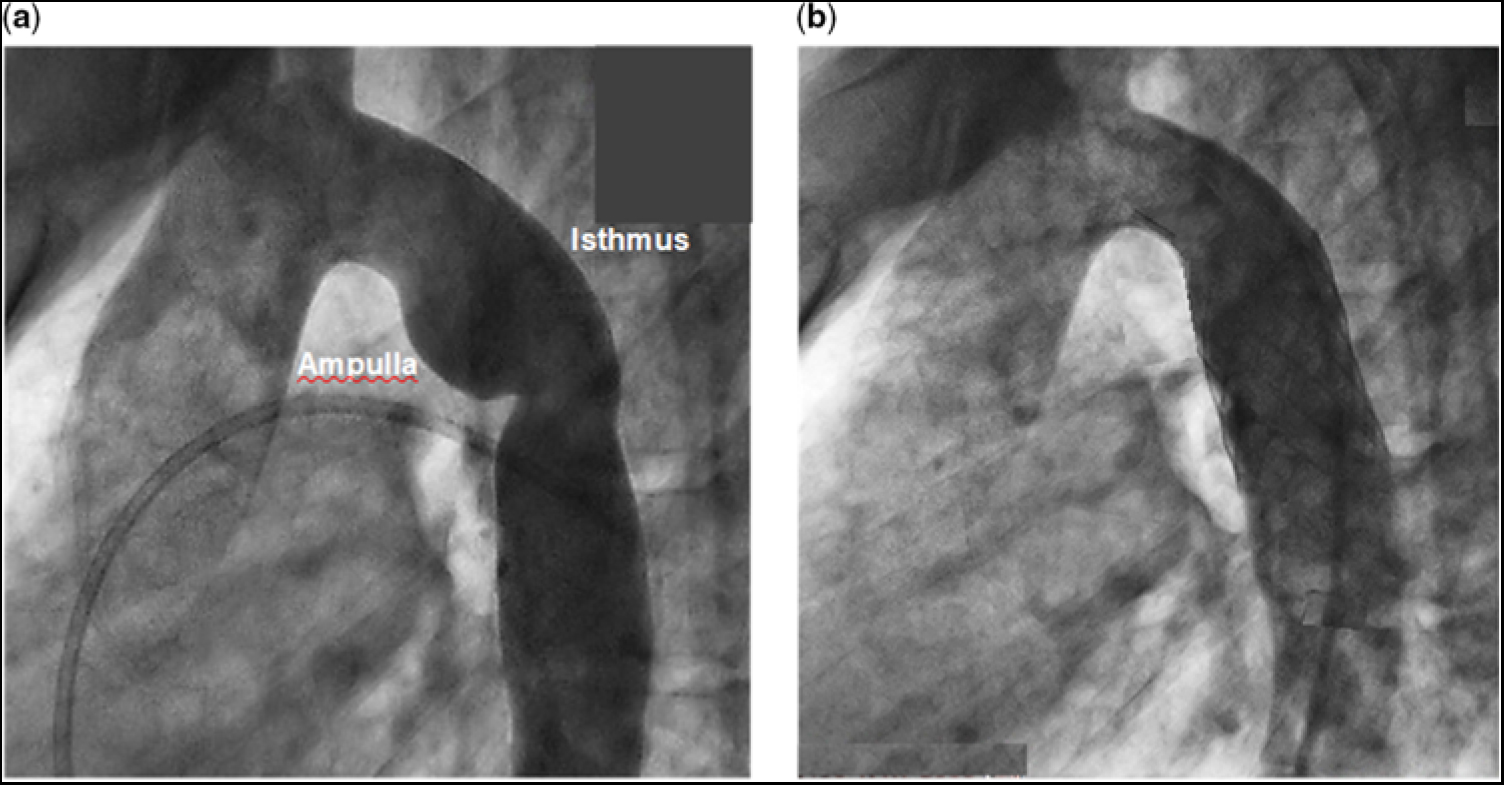

At cardiac catheterisation, with the patient under sedation, in vivo blood pressure measurements showed no obstruction across the aortic valve, an ascending aortic blood pressure of 78/50 mmHg, and a descending aortic pressure of 70/50 mmHg, by direct pull back. Angiography revealed a dilated ductal ampulla and discrete narrowing at the junction of the isthmus and the thoracic descending aorta (Fig 1a – see representative measurements in the caption). After reviewing the clinical information and the results of the computational fluid dynamics simulation studies, it was decided to treat the patient by catheter-directed stent implantation. A Palmaz P4010 XL stent (Johnson & Johnson, Miami, FL, United States of America) was chosen, which was manually mounted over a 22 × 5 NuMed BIB balloon (NuMED, Inc., Hopkinton, NY, United States of America) for insertion over a wire. A 16-French 70-cm Cook sheath (Cook Medical, Bloomington, IN, United States of America) was then advanced, under fluoroscopic guidance, over a 0.035 Amplatz Super Stiff exchange wire (Boston Scientific, Marlborough, MA, United States of America) that had previously been positioned in the right subclavian artery.

Figure 1. (a) Angiogram of the aorta with re-coarctation prior to stent implantation. Representative vessel diameter measurements, based on the cardiac catheterisation angiogram and the magnetic resonance imaging, are as follows: aortic annulus (entrance to the aorta), 17 mm; sinus of Valsava, 27 mm; sino-tubular junction, 18 mm; ascending aorta, 23 mm (at about the right pulmonary artery); proximal transverse aortic arch, 14 mm; distal transverse aortic arch, (entrance to the isthmus) 15 mm; the greatest distance from the wall of the ampulla to the lateral wall of the isthmus, 23 mm; narrowed distal isthmus, 13 mm; proximal thoracic descending aorta, 18 mm; distal thoracic descending aorta (exit from the aorta), 14 mm. (b) Angiogram of the aorta after stent implantation. There is a slight difference in angulation between the angiograms in (a) and in (b).

After unsheathing the complex, the stent was deployed at the desired location across the region of re-coarctation. The inner balloon was inflated to 6.2 atm followed by the outer balloon to 6.7 atm. After implantation, follow-up measurements showed the blood pressure in the ascending aorta to be 120/70 mmHg and descending aorta 120/70 mmHg. Follow-up angiography showed no residual region of abnormal dilatation or narrowing, and no evidence of a vascular tear, pseudo-aneurysm, or dissection (Fig 1b). The patient tolerated the procedure well and was discharged the following morning.

We employed a three-dimensional planar representation of the thoracic aorta, prior to endovascular stent implantation, based on magnetic resonance imaging, and the patient’s aortograms obtained at cardiac catheterisation, as displayed in Figure 1a. The modelled aorta was taken as tubular with a circular cross-sectional area. The aortic wall was considered rigid and impermeable. This approximation greatly simplified the computational process. Representative anatomic dimensions of the in silico model are detailed in the caption to Figure 1a.